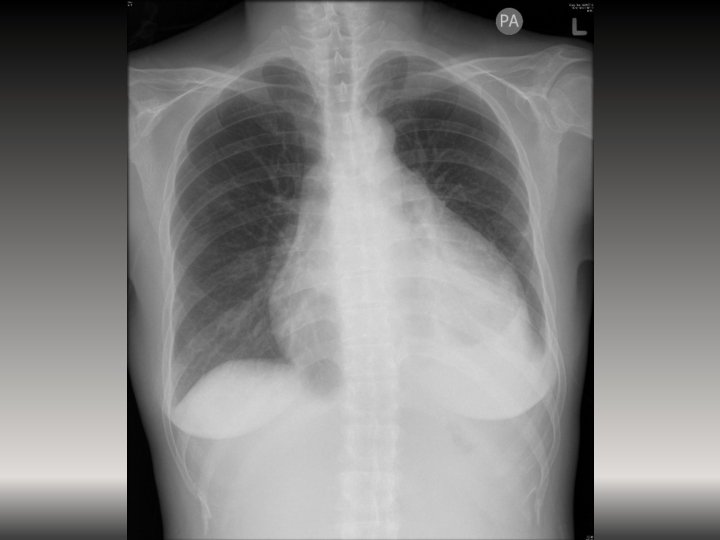

Case 4 • A 35 -year-old lady presented with fever for 2 weeks with

Case 4 • A 35 -year-old lady presented with fever for 2 weeks with epigastric pain. • T 40. 1 ⁰C BP 128/99 P 138/min • ECG was performed in triage because of tachycardia.

Case 4 2. What are the x-ray findings? (3 marks out of 4) 3.

Case 4 2. What are the x-ray findings? (3 marks out of 4) 3. What is the provisional diagnosis? (1 mark) 4. What are the possible causes of her diagnosis? (2 marks out of 3)